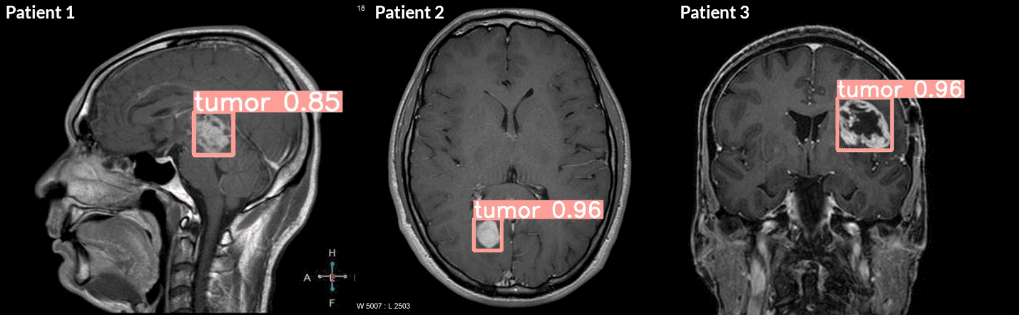

تحديد الكائن داخل الصور

يهدف تحديد الكائن إلى تحديد موقع الكائنات المختلفة في الصورة. تشمل بعض الأمثلة:

تُستخدم الرؤية الحاسوبية في المجال الطبي لتحليل الصور الطبية مثل الأشعة السينية والتصوير بالرنين المغناطيسي لتحسين التشخيص والعلاج.

- التطبيقات الطبية: من المحتمل أن يشهد المجال الطبي تقدمات كبيرة في استخدام الرؤية الحاسوبية لتحليل الصور الطبية وتشخيص الأمراض بدقة أعلى وسرعة أكبر.